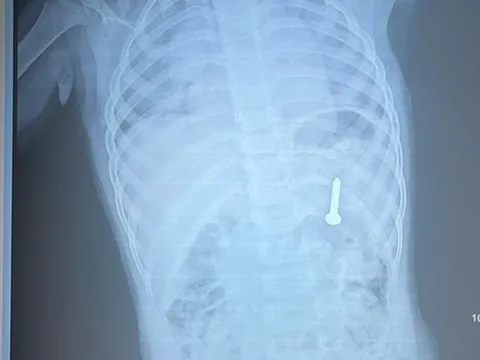

Kết quả thăm khám tại Bệnh viện K (Hà Nội) cho thấy khối u vú chiếm gần toàn bộ thể tích vú phải, kích thước khoảng 17-18 cm. Các xét nghiệm và chẩn đoán hình ảnh không ghi nhận tổn thương thứ phát, hạch nách chưa phát hiện bất thường. Kết quả giải phẫu bệnh xác định u phyllode lành tính.

Khối u vú được bóc tách, đường kính khoảng 18 cm. Ảnh: BVCC.

Bệnh nhân được chỉ định phẫu thuật cắt rộng khối u nhằm loại bỏ tổn thương, ngăn nguy cơ tiến triển và biến chứng. Do kích thước u lớn, kíp phẫu thuật phải tính toán kỹ để vừa đảm bảo lấy trọn khối u, vừa giữ lại tối đa mô tuyến nhằm bảo tồn tuyến vú và yếu tố thẩm mỹ.